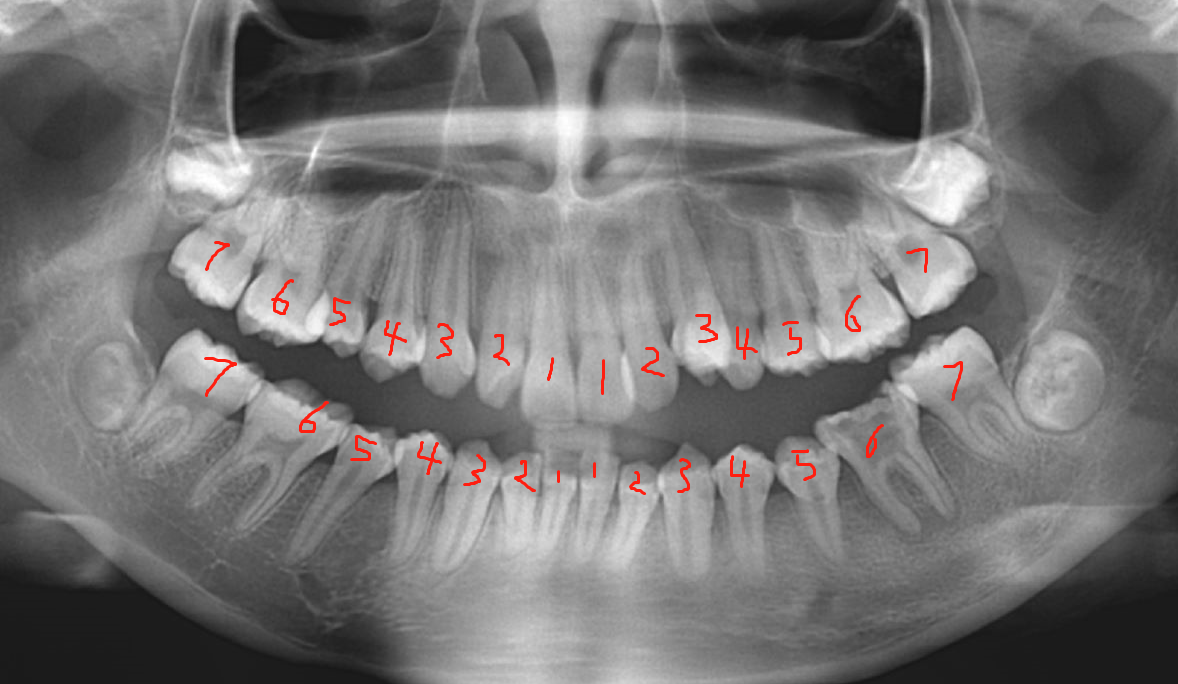

12岁左右,乳牙全部脱落,恒牙全部萌出(不含智齿),此时孩子口内共有恒牙28颗。

18岁左右,若是有智齿,智齿开始陆续萌出,智齿一共四颗,加上四颗智齿的正常人就拥有32颗牙齿。